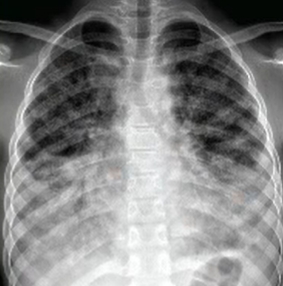

폐 섬유증이란 폐 조직이 딱딱하게 굳어가는 질환을 말합니다. 정상적인 폐는 스펀지처럼 부드러워 숨을 들이마실 때 잘 늘어나지만, 섬유화가 진행되면 폐가 탄력을 잃고 산소 교환 능력이 급격히 떨어집니다. 문제는 폐 섬유증 초기에는 단순한 체력 저하나 노화로 오해하기 쉽다는 점입니다. 가벼운 숨참, 마른기침 정도로 시작해 진단 시기를 놓치는 경우가 많기 때문에, ‘폐 섬유증이란 어떤 병인지’ 정확히 이해하는 것이 무엇보다 중요합니다.

폐 섬유증은 폐에 염증이 반복되면서 정상적인 폐 조직이 점차 흉터 조직(섬유조직)으로 바뀌는 질환입니다. 이 섬유조직은 고무처럼 탄력이 없고 단단해, 한 번 형성되면 정상 폐로 되돌아가지 않는다는 특징이 있습니다. 이로 인해 폐가 충분히 팽창하지 못하고, 산소를 받아들이는 능력이 점점 떨어지게 됩니다.

이러한 변화 때문에 폐 섬유증은 단순 염증성 질환인 폐렴이나 기관지염과 달리, 진행성·비가역적인 폐 질환으로 분류됩니다.